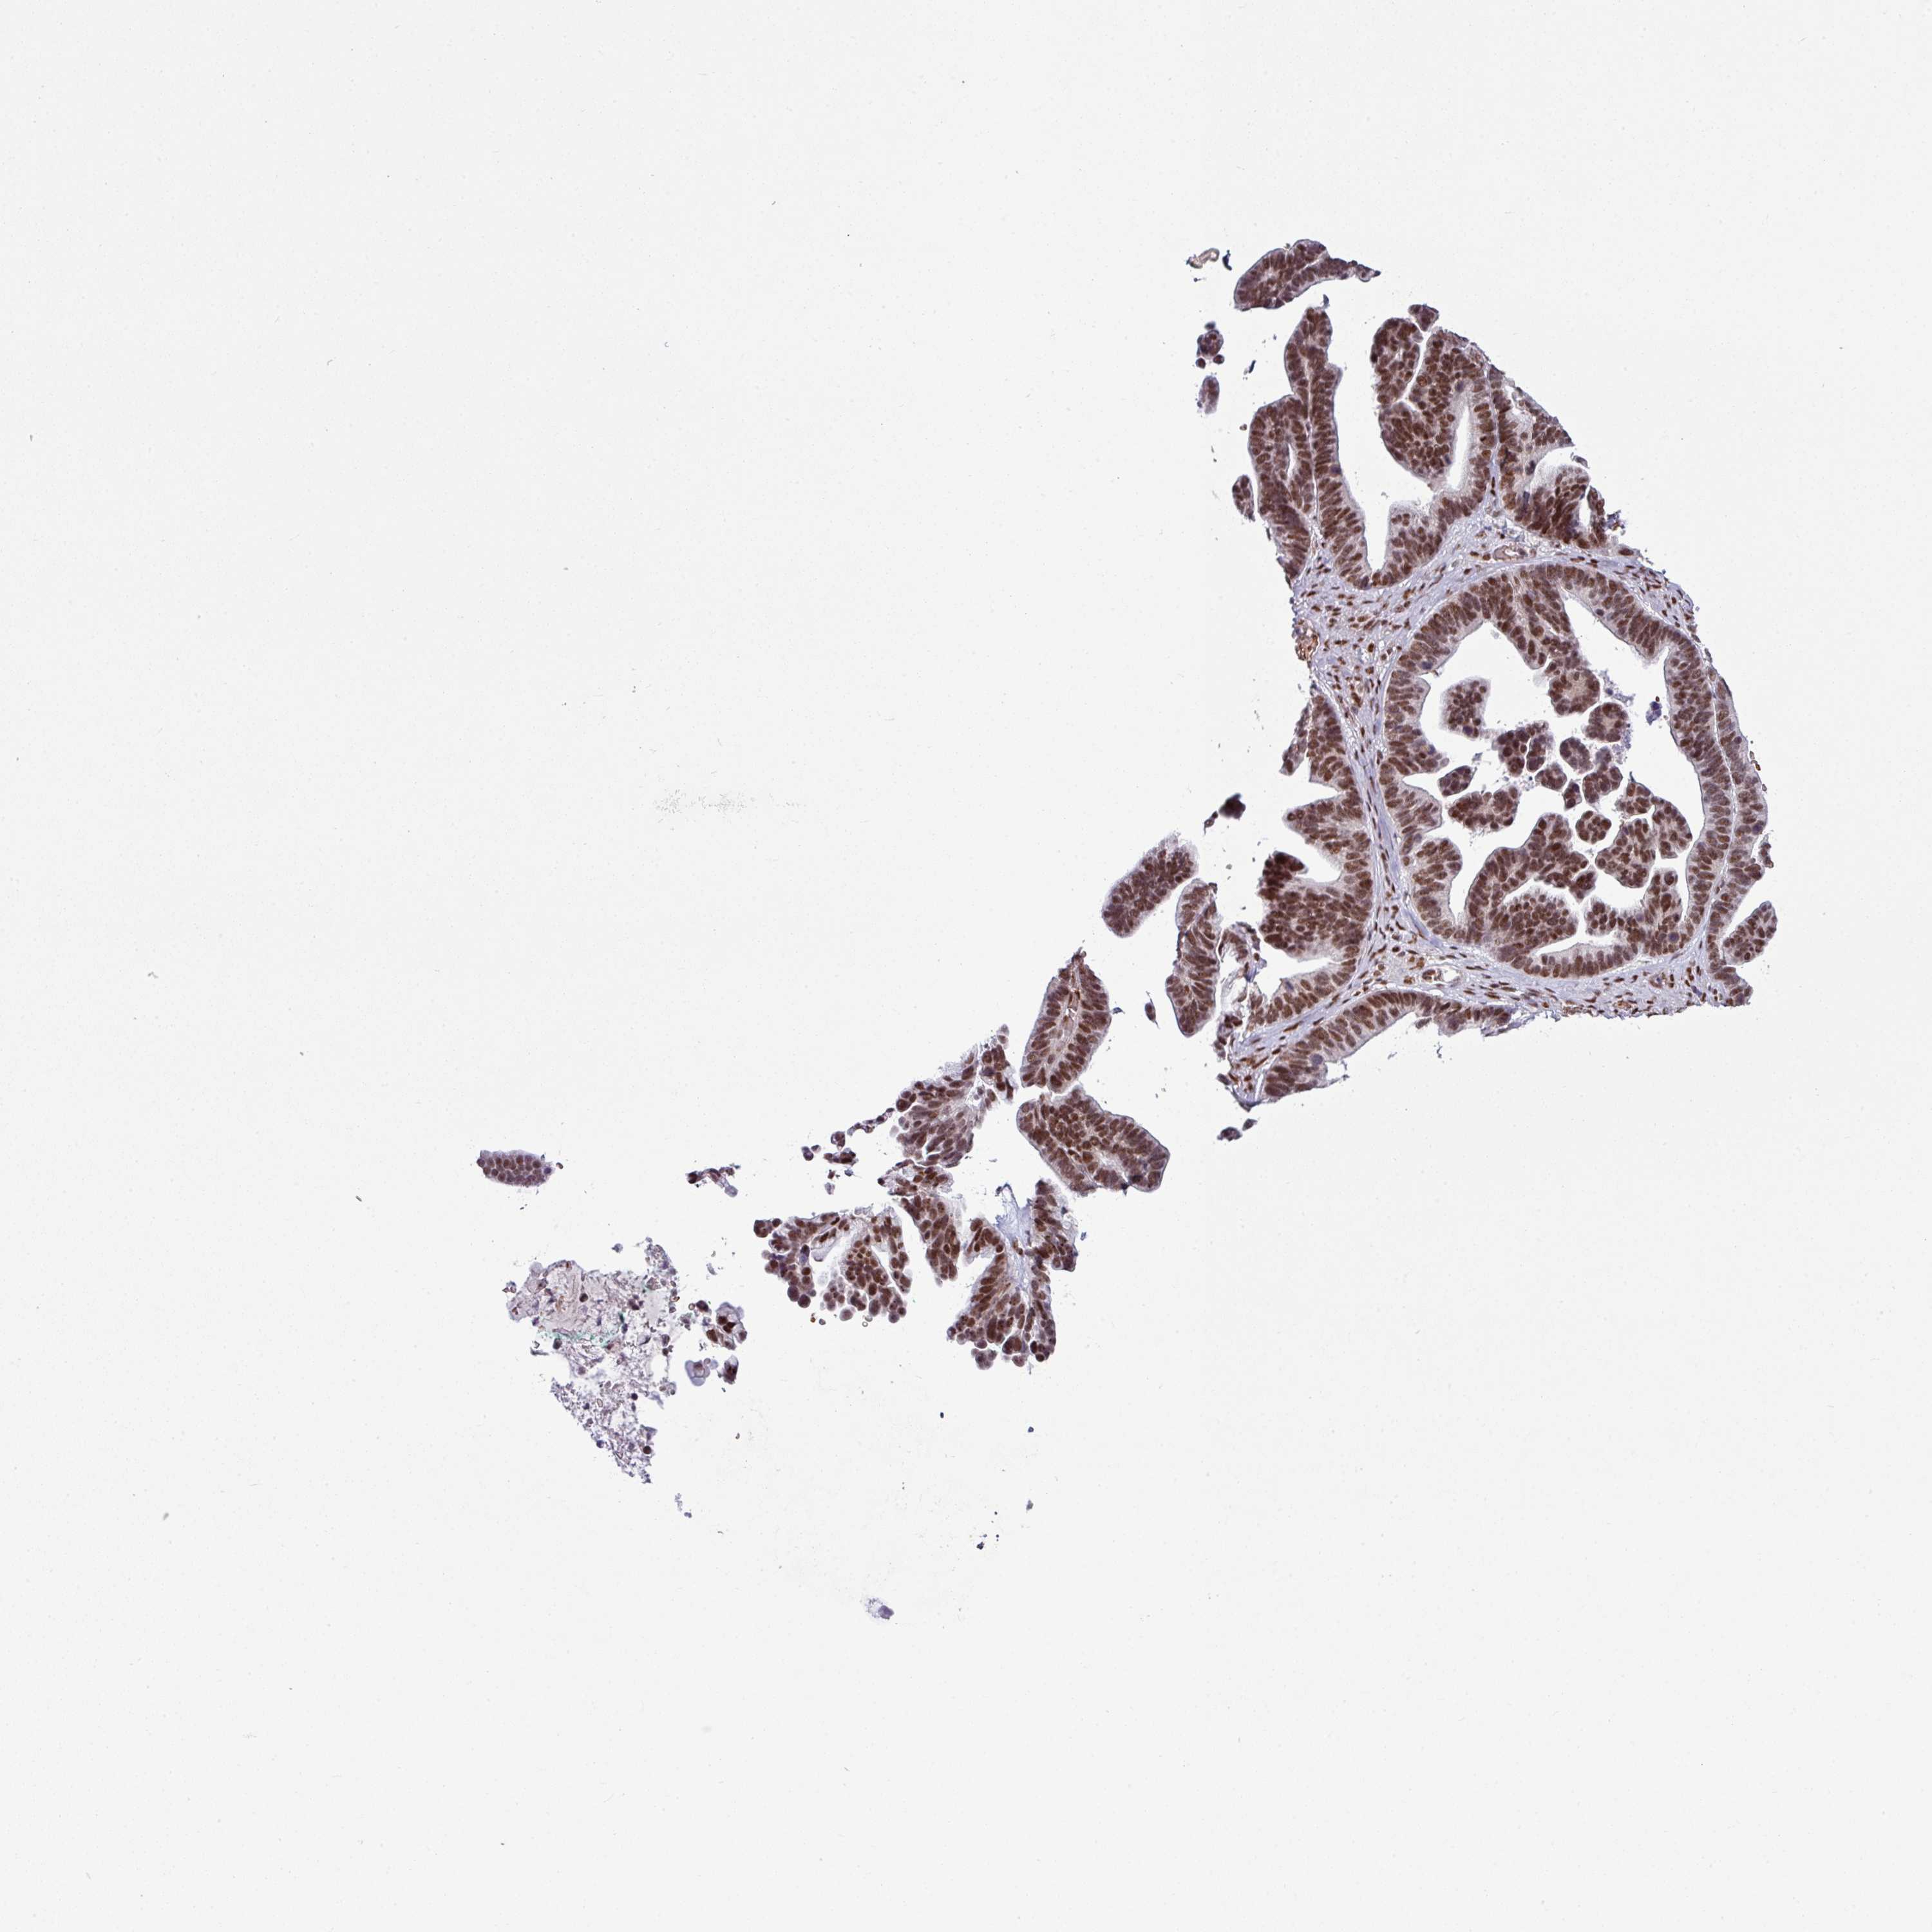

OVARIAN CANCER - Protein expressioni

A mouse-over function shows sample information and annotation data. Click on an image to view it in a full screen mode. Samples can be filtered based on level of antibody staining by selecting one or several of the following categories: high, medium, low and not detected. The assay and annotation is described here.

Note that samples used for immunohistochemistry by the Human Protein Atlas do not correspond to samples in the TCGA dataset.

Antibody stainingi

Antibody staining in the annotated cell types in the current human tissue is reported as not detected, low, medium, or high, based on conventional immunohistochemistry profiling in selected tissues. This score is based on the combination of the staining intensity and fraction of stained cells.

Each image is clickable and will lead to virtual microscopy that enables deeper exploration of all samples and also displays staining intensity scores, fraction scores and subcellular localization as well as patient and tissue information for each sample.

Antibody HPA051406

Staining

High

Medium

Low

Not detected

Intensity

Strong

Moderate

Weak

Negative

Quantity

>75%

75%-25%

<25%

None

Location

Nuclear

Cytoplasmic/membranous

Cytoplasmic/membranous,nuclear

Cystadenocarcinoma, serous, NOS

Carcinoma, NOS

Cystadenocarcinoma, mucinous, NOS

Carcinoma, endometroid